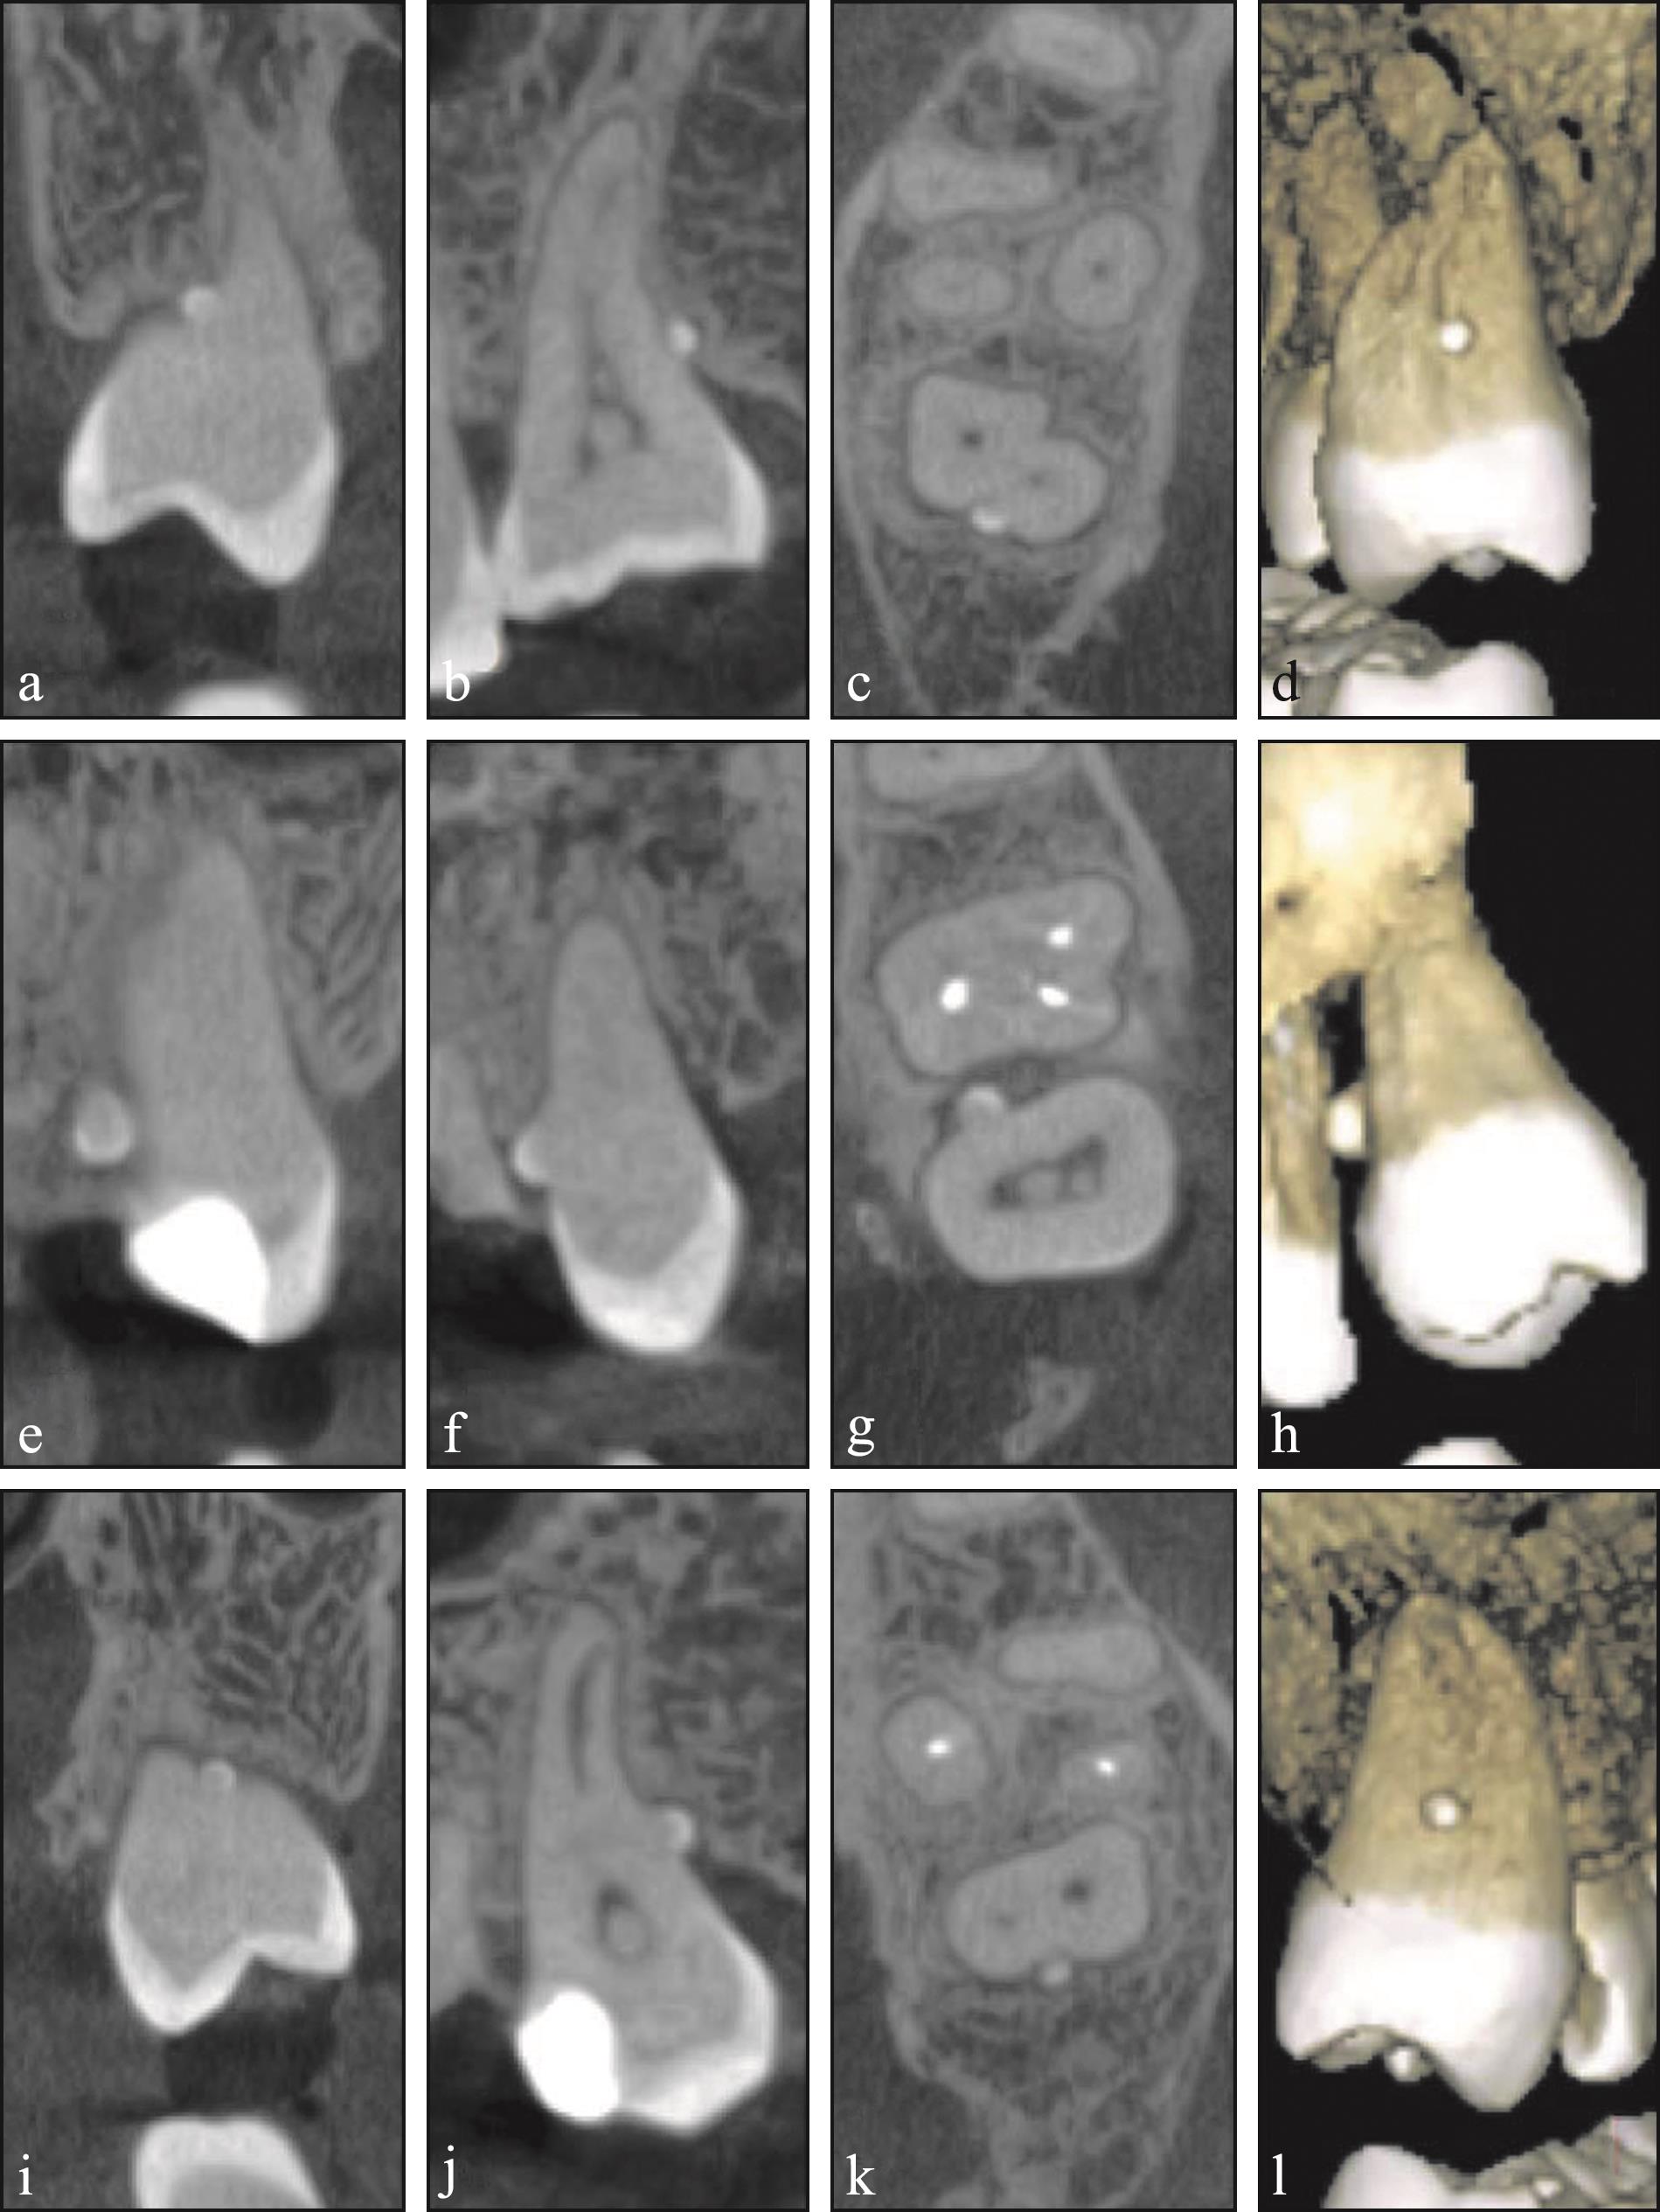

Fig 3

Diagrams of structural relationship between cementum and enamel pearl"